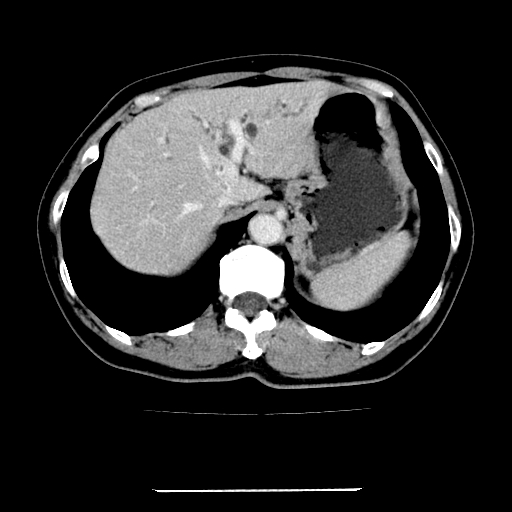

标题: CT22301:女,67岁,上腹部疼痛一周伴皮肤黄染,无发热。 [打印本页]

女,67岁,上腹部疼痛一周伴皮肤黄染,无发热。

左叶肝内胆管结石,并远端肝内胆管扩张。

考虑:肝内胆管结石继发肝内胆管扩张,右肾旋转不良。

肝内外胆管结石并肝内胆管扩张。

建议薄层观察,除外肝门部胆管细胞癌

考虑肝胆管癌;胰头占位?【形态失常,体积增大】

1、肝门高密度影下层面和胰头层面可见轻度胆管扩张,而静脉和延迟期均未见扫描完胰头,不能完全排除胰头占位。2、肝门部高密度影,考虑钙化或结石。

考虑肝门胆管癌伴门脉左支受侵包埋,建议mrcp进一步检查。